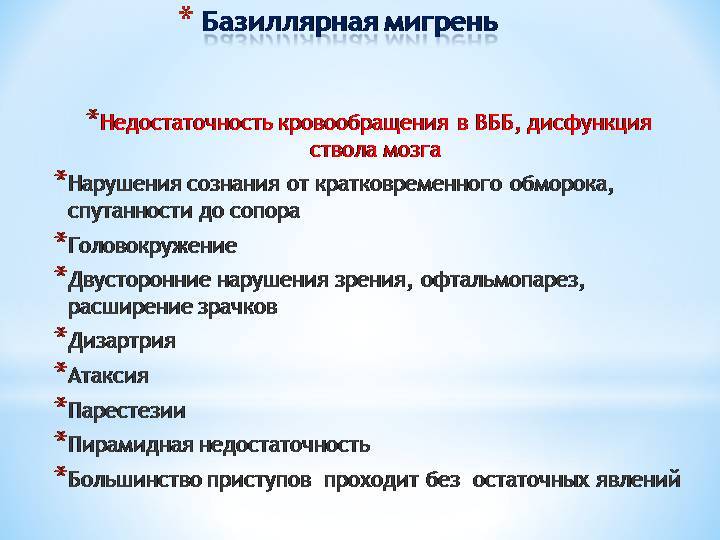

Пирамидная симптоматика в неврологии: ключевые аспекты